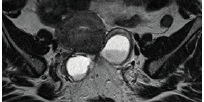

IRM 3D et cartographie de l’endométriose

L’examen est le plus souvent réalisé dans le bilan de douleurs pelviennes chroniques évocatrices mais également dans les bilans d’infertilité. La cœlioscopie est remise en question en tant que gold standard diagnostique, et devenue thérapeutique avec exérèse complète des lésions nécessitant une cartographie préalable fi able. Le diagnostic des localisations ovariennes est aisé en imagerie devant un hypersignal T1 franc pathognomonique d’endométriome (figure 1).

Les progrès de l’imagerie sont liés à l’amélioration de la résolution spatiale avec des séquences en coupes fines millimétriques dans le plan des ligaments utéro-sacrés (figure 1) et des séquences isotropiques 3DT2 permettant une analyse plus fine par des reconstructions multiplanaires en post traitement.